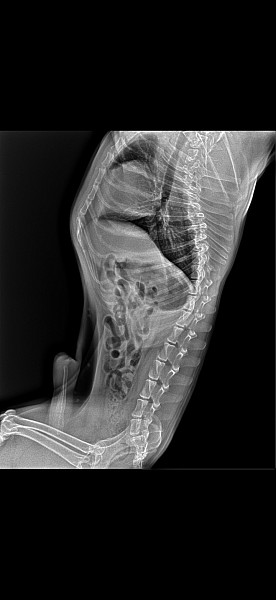

Вечером он смог сам пописать во дворе.На утро повторился приступ: он стал ходить по кругу,тыкаясь лбом в углы стен,потом зачавкал,и обмяк.Судорожный припадок был около 2 мин.глаза закатились,голова откинута.Я вколола ему сульфат магнезии 1,8 куб.Припадок прошел,но собака долго лежала без движения после. После этого он сам вставал ходил пить воду,но рвота,теперь уже не кофейной гущей а желчью с водой.мы перепугались и поехали еще в другую клинику.Мордочка у него уже вернулась в обычное состояние,без тика.Спазм горла прошел.Была сильная слабость,он висел на руках. Там сказали что эпилепсия,плюс угробленные препаратами печень и почки.Взяли новый анализ биохимия и общий (второй на фото) Сделали рентген,на нем обнаружилась игла,но они на этом не заострили внимания.Температура была 39. Назначили капельницу 200мл Физраствора,укол амоксициллина и квамотел.Сказали приезжать на сл.день на капельницы.Ночью он был в забытьи,глаза были закатаны,как глубокий сон.Утром он проснулся,нас узнавал.Мы ему скормили баночку бульона,он с удовольствием выпил из шприца,облизывался.Но после еды,примерно через 20 мин снова началось типа прострации:он стал ходить вокруг комнаты,стоять уткнувшись головй в стену,его начало потряхивать,я испугалась и впрыснула несколько разведенных капелькорвалола за щеку.Приступа как такого не случилось,он упал на бок,было хриплое дыхание.Потом сердце остановилось у нашего бульдога(((( Пожалуйста,подскажите,что же это такое было,можно ли было его спасти,от чего судороги такие? Если от печени,то до этого он был абсолютно здоровым. Или шунт может так быстро развиться?И желтизны склер и ушей не было до последнего момента. Могла игла вызвать судороги? Очень надеюсь на Ваш ответ!